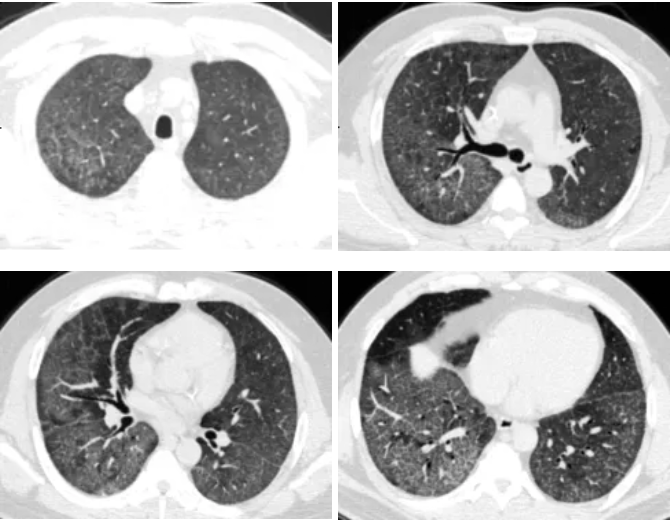

▲ 灌洗后胸部CT

术后患者生命体征稳定,已完全脱离氧气,日常生活无明显闷喘。